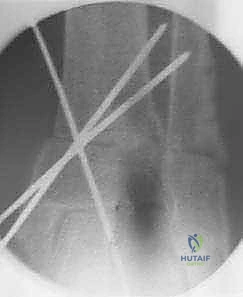

باستخدام أدوات قطع عظمية دقيقة جداً (مناشير جراحية متأرجحة)، وتحت توجيه جهاز الأشعة السينية المباشر في غرفة العمليات (C-arm)، يتم إحداث القطع في عظم الظنبوب في المكان المخطط له مسبقاً، مع الحفاظ على جزء بسيط من القشرة العظمية في الجهة المقابلة لتعمل كمفصلة (Hinge).

5. التثبيت الصلب وزراعة الطعم العظمي

في حالة "فتح الإسفين"، يتم وضع طعم عظمي (يؤخذ غالباً من عظم الحوض للمريض أو طعم صناعي متقدم) لملء الفراغ. بعد ذلك، يقوم الدكتور هطيف بتثبيت العظم في وضعه الجديد القويم باستخدام شرائح معدنية تشريحية مصممة خصيصاً لهذه المنطقة (Anatomical Locking Plates) ومسامير قوية. هذا التثبيت الصلب يضمن التئام العظم بشكل صحيح.